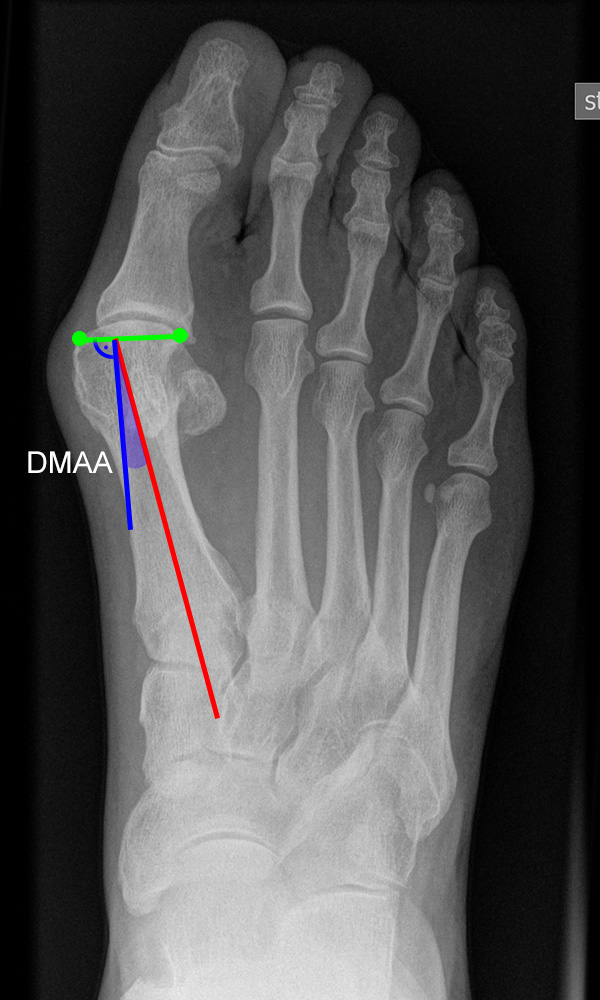

Gelenkflächenwinkel

DMAA (Distal metatarsal artikular angle, Syn. Gelenkflächenwinkel): Winkel zwischen der Achse des Os metatarsale I (rot) und dem Lot auf die distale Gelenkflächenebene (blau) des Os metatarsale I. Die Gelenkflächenebene (grün) wird definiert durch zwei Punkte, welche die mediale und laterale Begrenzung der Gelenkfläche definieren (Norm: <10° 5). Die Projektion des DMAA ist stark abhängig von der Rotation des Os metatarsale I 7. Daher ist bei der operativen Behandlung des Hallux valgus eine Beurteilung häufig erst nach Korrektur der Pronationsstellung des Os metatarsale I möglich. Tendenziell wird der DMAA auf präoperativen Röntgenaufnahmen überschätzt.